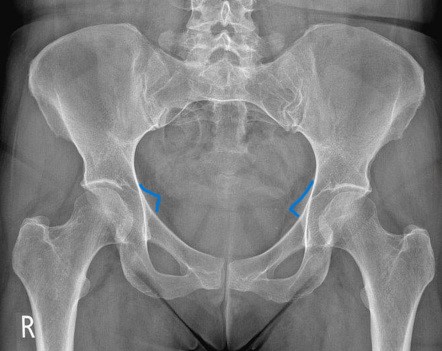

What anatomical structure is outlined in blue?

ischial spines